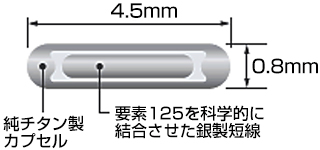

密封小線源療法とは何ですか?

小さな線源を前立腺内に挿入し、前立腺内のがん病巣へ線源から放射線を照射する放射線治療です。